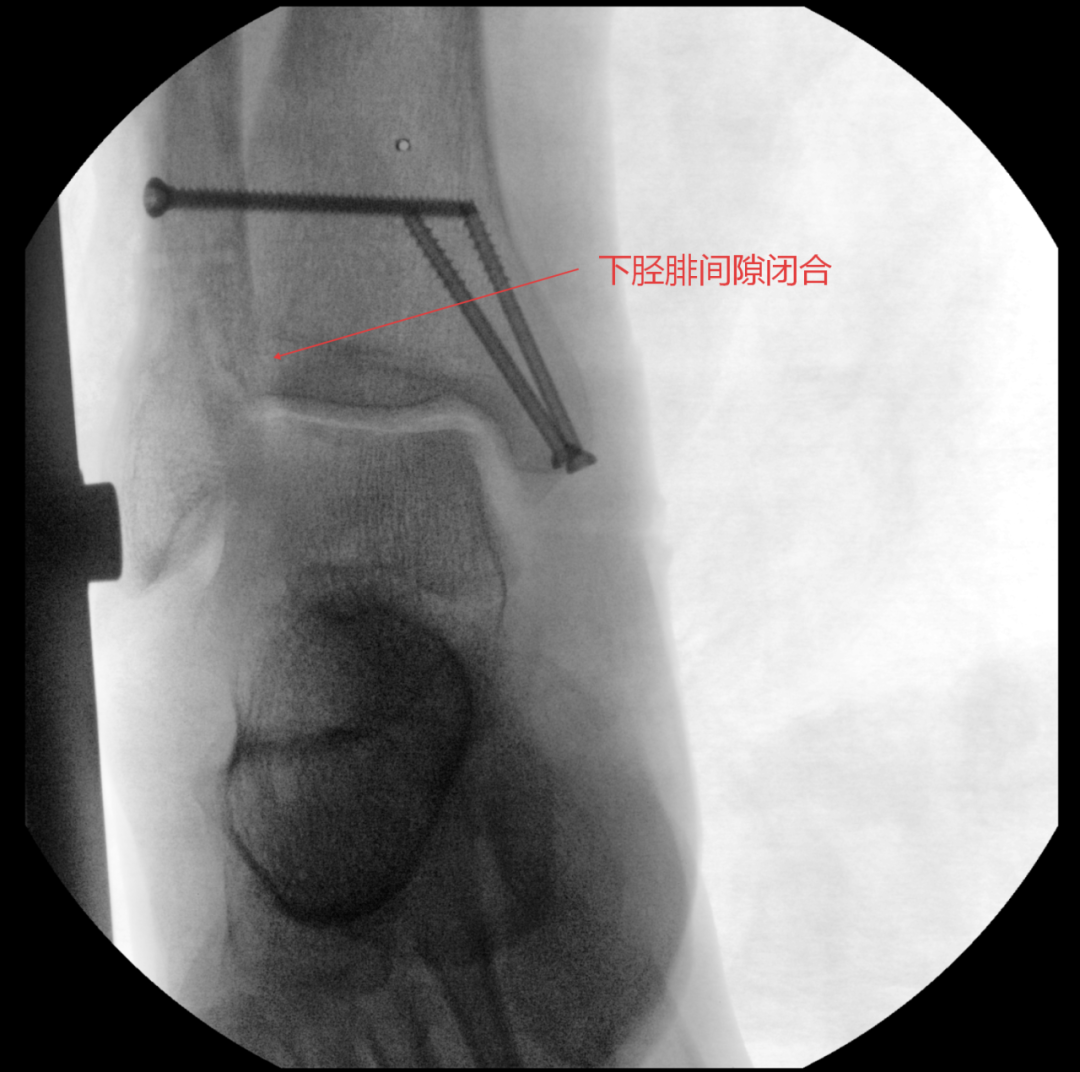

随后,医疗团队为王大爷开展手术治疗。

术中进行下胫腓拉力试验结果呈明显阳性,且复位效果未达预期,团队当机立断决定切开探查,发现前结节骨折块嵌顿于下胫腓间隙,正是阻碍复位的关键,取出骨折块后顺利完成复位,手术按规范流程顺利结束。